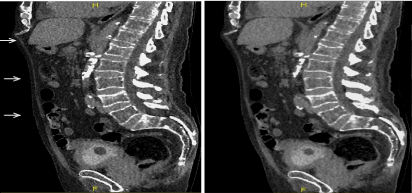

Qualitative evaluation: (Figures 5, 6)

Figure 5. Qualitative evaluation

Figure 5a. Excretory WV mode –sagittal view –result of the automatic stitching (a1). The junctions between volumes are recognized at certain levels (→ white arrow); after additional manual stitching (a2); the junctional zones have disappeared.

Figure 5b. Qualitative evaluation between helical acquisition unenhanced (b1) and excretory WV mode (b2). There is no visual difference for a clinical purpose between those two acquisition modes.